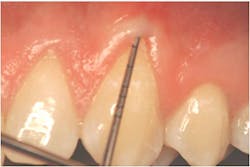

"Recession of the gingiva is becoming a prominent condition in the oral health of many patients and should be treated at its earliest detection," according to A.P. Saadoun in "Current trends in gingival recession coverage - Part I: the tunnel connective tissue graft."5 Saadoun also says the ideal time to correct gingival recession is at a Class I-II, which is less traumatic surgically for the patient, and which achieves predictable regenerative results (see Figures 1, 2).

The A.C.E. starts with marginal tissue evaluation to identify true recession. Using a periodontal probe, take the first measurement from the cemento-enamel junction (CEJ) to the gingival margin on the facial and lingual, and record.

Secondly, gently retract the patient's lip or cheek to gain access, place the periodontal probe on the outside of the tissue, and measure from the gingival margin to the mucogingival junction, and record (see Figure 3).

Thirdly, measure the clinical probing depth (pocket depth to the sulcus) (see Figure 4). To calculate the attached gingiva, subtract the probing depth from the outside measurement of the gingiva for the total width of of attached gingiva. Record the width of the attached gingiva and identify any teeth that need tissue regeneration, such as root coverage surgery (see Miller classification I-III, Table 1).